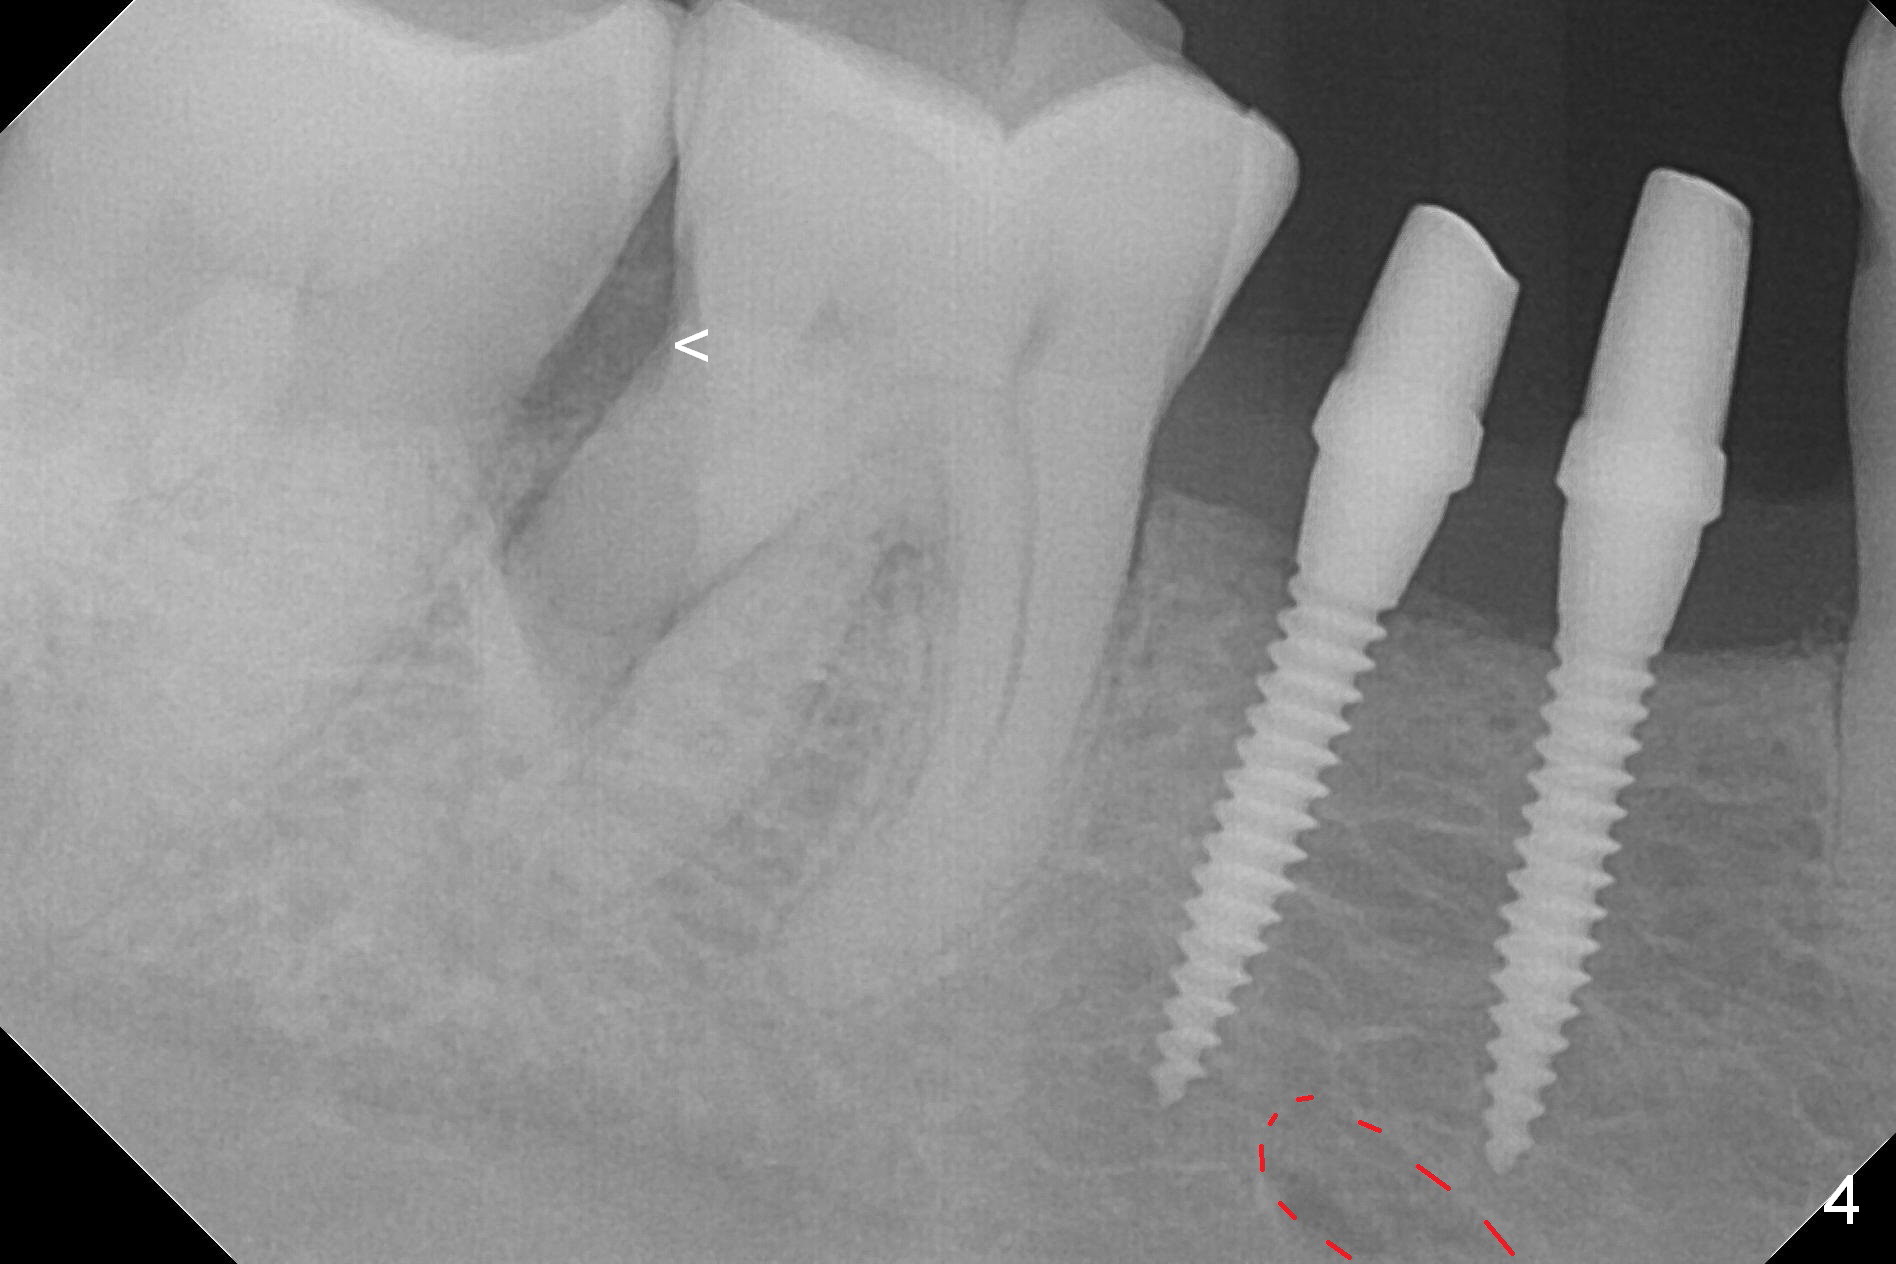

The wide mesiodistal space at #29 is most likely due to congenital missing permanent tooth (i.e., deciduous molar retention before extraction 34 years ago). The patient is now 62 years old. In fact the buccolingual width is not so narrow (Fig.1). After incision, the ridge is approximately 5 mm. Two osteotomies are established with 1.2 mm drill at 8 mm mesially and 1.5 mm one at 10 mm distally (Fig.2). The apparent approximation of the mesial osteotomy to the Mental Loop (red dashed line) is related to X-ray angulation, since there is 1-2 mm separation when two of 2x10(2) mm 1-piece implants are placed (Fig.3,4). Insertion torques of the mesial and distal implants are less than 25 and 15 Ncm, respectively. In fact bone graft is placed around the distolingual root of the tooth #30 after calculus removal (Fig.4 <). Following reduction of the abutments, periodontal dressing is applied locally. The dressing dislodged 13 days postop (Fig.5). A provisional is going to be fabricated 4 weeks postop when the wound heals (Fig.6). No bone loss is observed 4 months postop (Fig.7).